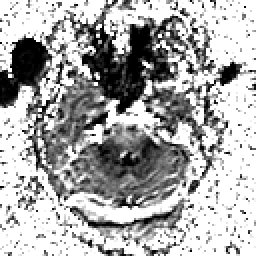

Alzheimer's Disease: SPECT/fMRI overlay -- Slice #1